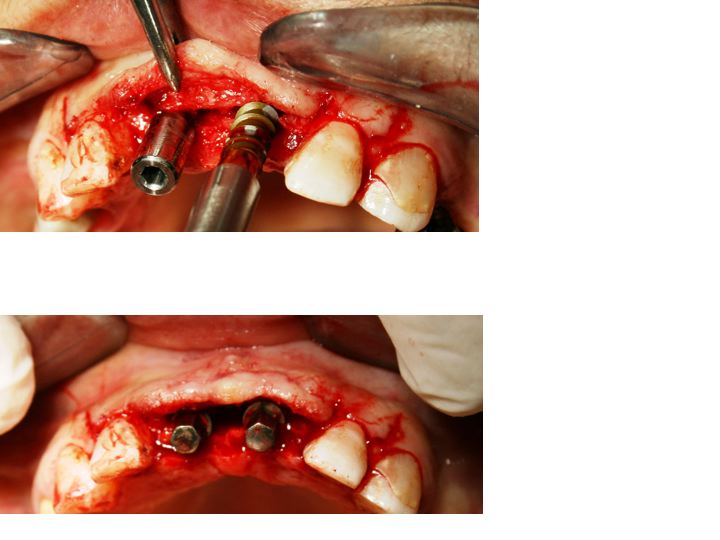

Split-crest technique associated to immediate implant positioning and temporising. Use of oral electro-welding to stabilize implants during healing time. A case report. Avvanzo P. Abstract Implant rehabilitation of the edentulous maxilla may be somewhat problematic because of anatomic situations involving insufficient bone thickness or mandibular teeth position. One approach in this situation is localized horizontal ridge augmentation with the split crest technique. This surgical approach allows the external cortical plate of the maxilla to be moved in a buccal direction to gain an increase in width to introduce implants of appropriate diameter and with an appropriate angle in spite of lower arch. We tried to associate split crest technique to immediate implant positioning and temporising using an oral electrowelder to stabilize implants during healing time. Introduction Bone resorption in anterior maxillar edentulous areas can be so important to affect implant diameter and position choice, which may not be ideal for the teeth to be replaced. The result can be a failing position and a smaller diameter than necessary. Another failing result is an insufficient esthetic aspect of the tooth-gingiva architecture being resorbed the washboard form of the flattened alveolar bone. If bone graft techniques are not considered, the first option treatment is the thikness augmentation separating the cortical plates and creating a space which can be filled with bone , bone substitutes or left opened using implants as space keeping devices. In all cases no load has to be applied(R) on the area. The Split crest technique is undoubtly an advantageous procedure to obtain a correct alveolar bone thickness in resorbed edentulous ridges avoiding in the same time bone grafts from donor sites reducing morbility for a second surgical area and diminishing the size of incisions in the first one. It takes advantage of the growth potential of bone when undergoes to osteogenetic distraction and it has the same healing pattern of extraction sites. Since the space between the two cortical plates is still not mature bone the standard protocol is to permit healing and maturing before implant placement. There are a lot of modifications to this technique regarding bone substitutes or direct implant positioning avoiding the direct load on the area. The technique explained in this case report schedules the use of conic, large screw, single stage implants, placed after the crest splitting and immediately temporised. In multiple implants positioning, to avoid micro-movements on immediate loaded implants a titanium bar has been electro-welded to the abutments temporarily, thus creating a solidarised system even stronger than single implants. Even if in this case report the cortical plates were thick and solid, the chance for micro movements was real, since implant restorations involved the upper central incisors and their ability to engrave food. Since it is quite difficult divert food incision to other teeth when such central teeth are involved in restoration, it was decided to use electro-spot-welding to solidarise implants.